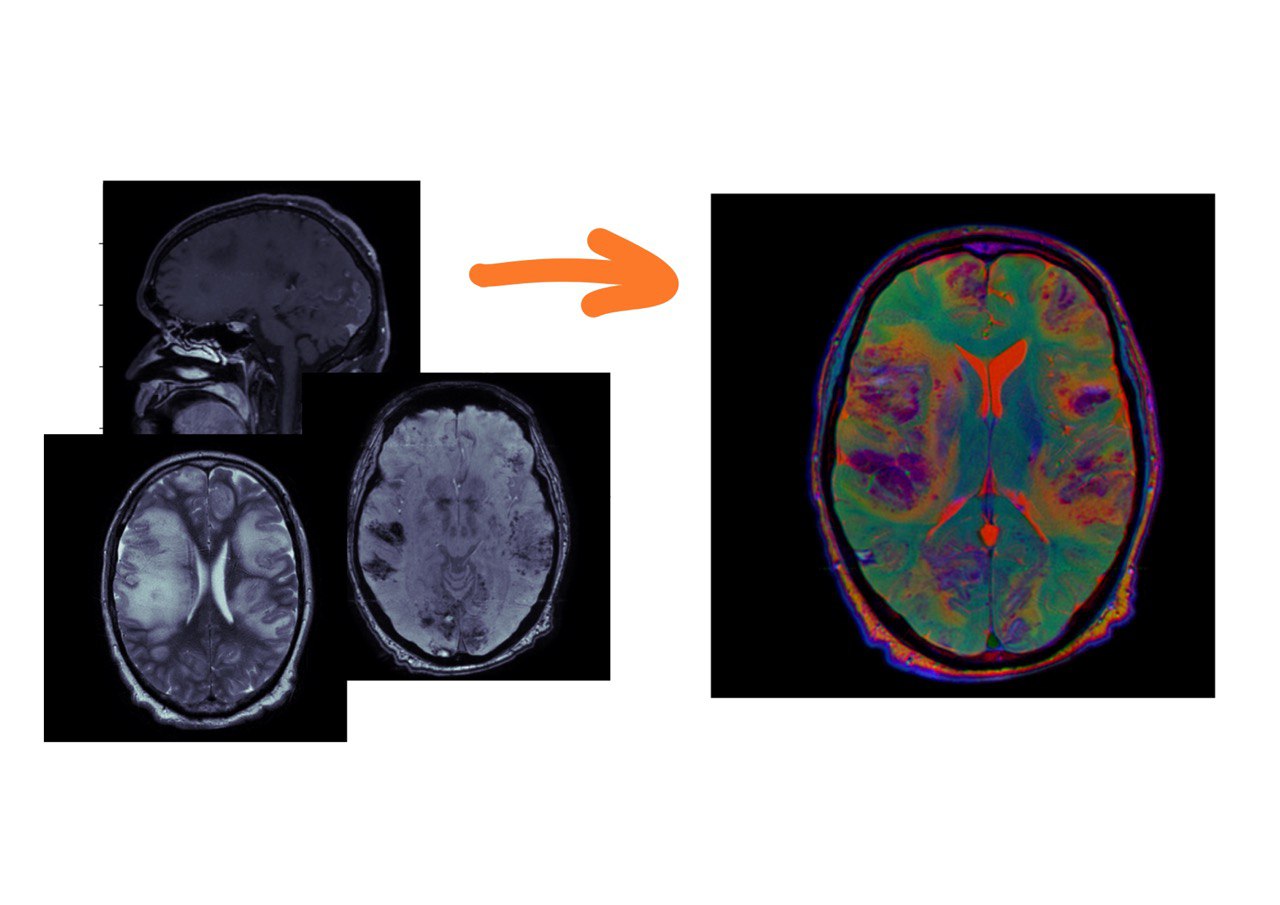

Для наглядности я взял T1 с контрастным усилением, SWI и T2. Т1-взвешенная серия нарезана сагиттально, SWI и Т2 – аксиально.

Три серии

Каждая из этих серий содержит полезную информацию, и мы хотим показывать нейросетке все три взвешенности. Для этого их нужно подавать как каналы (примерно так, как делал фотографии Прокудин-Горский в начале 20 века: делал три фотографии через разные светофильтры, а потом накладывал их друг на друга).

Прокудин-Горский

Понятно, что для этого серии должны быть ориентированы идентичным образом. Сейчас покажу, как это можно сделать.